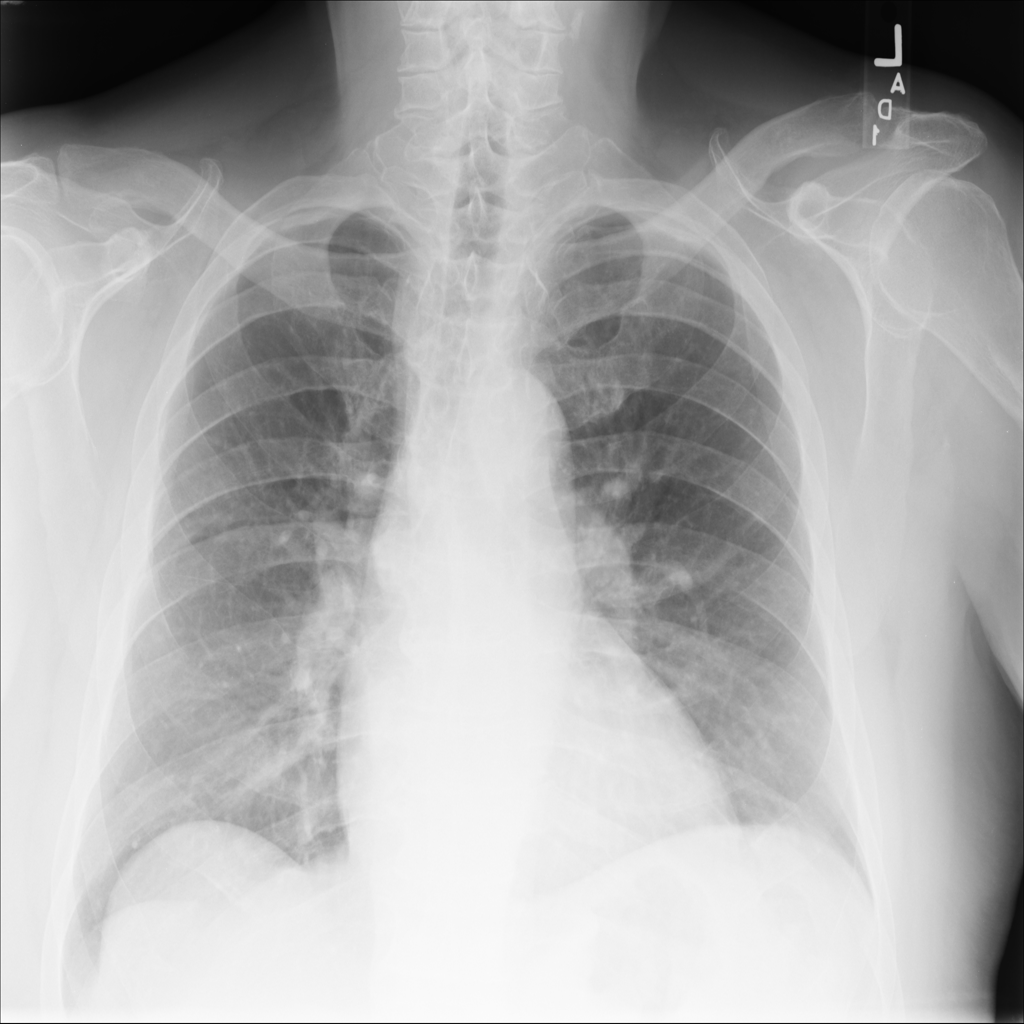

PAT-4639 · IMG-045Cardiomegaly

PAT-4639 · IMG-045

PA